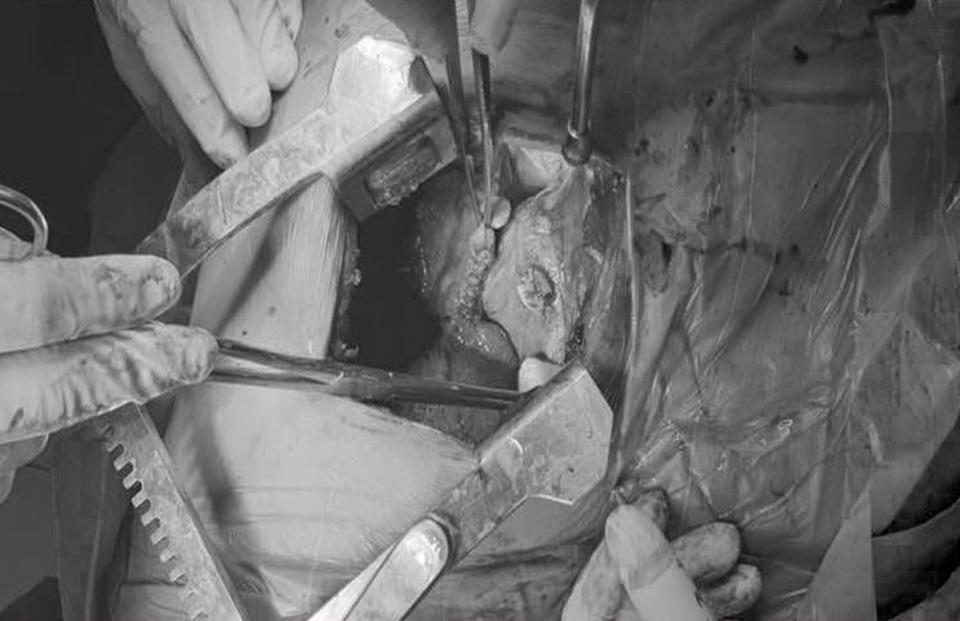

Nhát dao sắc lẹm đã đâm xuyên tim, thấu phổi bệnh nhân

Sau khi mở lồng ngực thám sát, ê kíp phát hiện tại vùng tâm thất trái của tim có vết thương lớn (khoảng 2cm) đang xuất huyết ào ạt. Nhát dao sắc lẹm sau khi đâm thủng tâm thất tiếp tục xuyên thấu phổi. Vết thương nguy hiểm đe dọa trực tiếp tính mạng bệnh nhân, nguy cơ ngưng tim, tử vong ngay trên bàn mổ. Bệnh nhân đã may mắn được ê kíp khâu vết thương tim, vết thương phổi, tiến hành cầm máu, đóng lồng ngực.